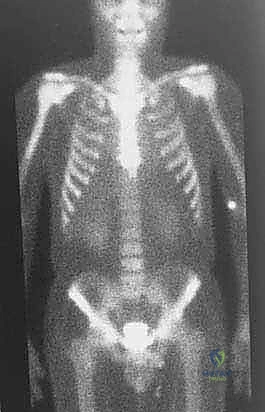

| الانتشار (النقائل) | لا تنتشر لأعضاء أخرى | تنتشر غالباً إلى الرئتين أو عظام أخرى |

3. الانتشار (Metastasis - M): هل انتقل الورم لأعضاء أخرى (M0 لا يوجد، M1 يوجد انتشار)؟

يتم تقييم مدى استجابة الورم للعلاج الكيميائي (Tumor Necrosis Rate) بعد الاستئصال، وهو مؤشر قوي لفرص الشفاء التام.